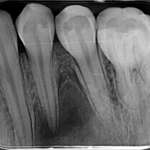

Le perforazioni iatrogene – Diagnosi e terapia

Oggi grazie a nuovi materiali, strumenti e tecnologie, la prognosi delle perforazioni è notevolmente migliorata. Molti casi, che anni...